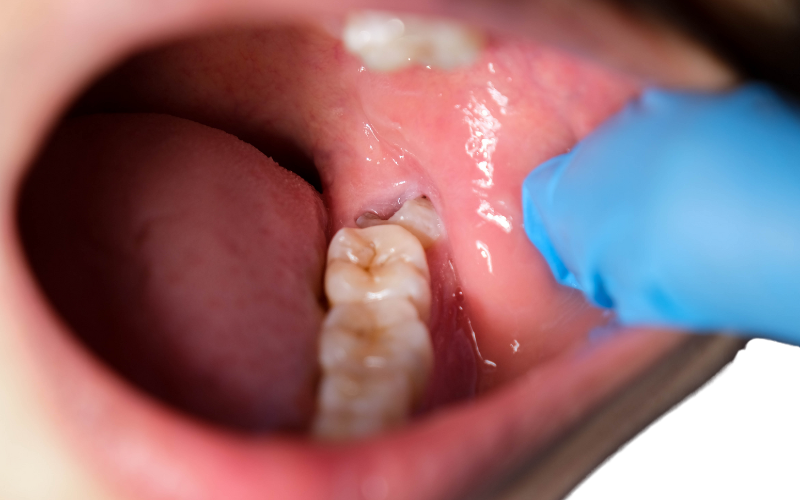

Swollen or Bleeding Gums – Signs of infection or gum irritation.

Impacted Wisdom Teeth – Teeth stuck under the gums or growing at an angle.